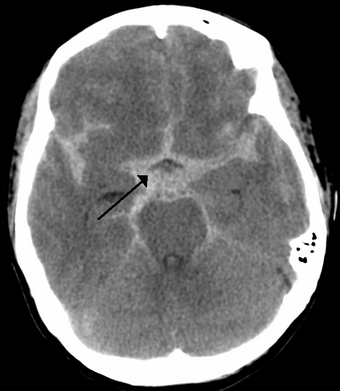

CT scan of the brain showing subarachnoid hemorrhage as a white area in the center (marked by the arrow) and stretching into the sulci to either side